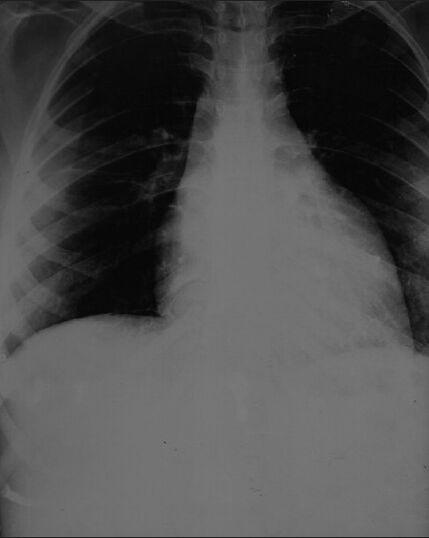

Peripartum cardiomyopathy (PPCM) is a disease of unknown etiology which affects pregnant females during late pregnancy or during the first 5 months post-partum. The clinical presentation of these patients is similar to that of patients with dilated cardiomyopathy. Anesthetic management of such cases poses a challenge; due to the increased risk of various perioperative complications. We report the successful anesthetic management of lower segment caesarean section in a patient with PPCM.

围产期心肌病(PPCM)是一种病因不明的疾病,影响妊娠晚期或产后前5个月的孕妇。这些患者的临床表现与扩张型心肌病患者相似。此类病例的麻醉管理具有挑战性,因为围手术期各种并发症的风险增加。我们报告了1例围产期心肌病患者成功实施下段剖宫产术的麻醉管理情况。